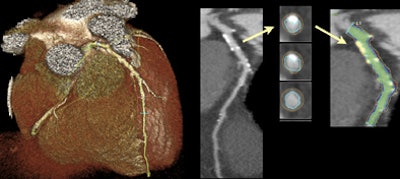

| Above, scatterplot of estimated versus measured calcium scores. The correlation is excellent both at high and low calcium scores. Below, difference in calcium score estimate and measured calcium score (Bland-Altman type plot). Also shown is the 95% reliability of traditional calcium scoring itself (from the MESA validation study -- Chung et al, AJR, 2008, Vol. 190). Almost all calcium score estimates lie within these limits. Both the inter- and intraobserver reliability of the new technique, as assessed by the intraclass coefficient, were 0.99. |

The results showed a range of measured calcium scores from 0 to 4,842. The resulting Pearson's coefficient (R2) of the regression of the two measurements was 0.99. Moreover, the accuracy of the technique to classify coronary calcium into standard risk and was near perfect (kappa 0.88). Finally, a Bland-Altman analysis showed nonsignificant bias, the authors reported. Both the inter- and intraobserver reliability of the new technique, as assessed by the intraclass coefficient, were 0.99.